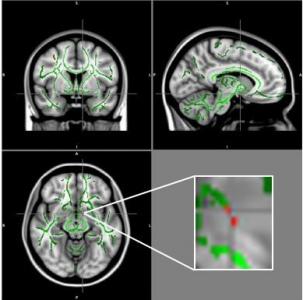

L'étude menée à l'Université de Sao Paulo au Brésil auprès de 59 adolescents obèses âgés de 11 à 18 ans et 61 adolescents témoins en bonne santé, appariés pour le sexe, l'âge, la catégorie socioéconomique et le niveau d'éducation a évalué chez ces participants l'intégrité de la substance blanche du cerveau par imagerie du tenseur de diffusion (DTI). Cette technique d’imagerie permet de mesurer l'anisotropie fonctionnelle (AF), le mouvement microscopique, ou l'anisotropie, des molécules d'eau à l’intérieur et autour des fibres de la matière blanche du cerveau. Les valeurs AF basses indiquent une plus grande perturbation dans la matière blanche.

Cette analyse révèle une perte d'intégrité de la substance blanche dans plusieurs zones du cerveau chez les jeunes patients obèses. Comparé à ceux de témoins en bonne santé, les cerveaux des adolescents obèses présentent une réduction des valeurs de l’AF dans plusieurs zones du cerveau dont l'amygdale, l'hippocampe, le thalamus, le gyrus cingulaire, le fornix, l'insula, le putamen, le gyrus orbitaire et l'hypothalamus bilatéral. Or, plusieurs de ces zones sont impliquées dans la régulation de l'appétit, le contrôle des impulsions, les émotions et la récompense et le plaisir de manger.